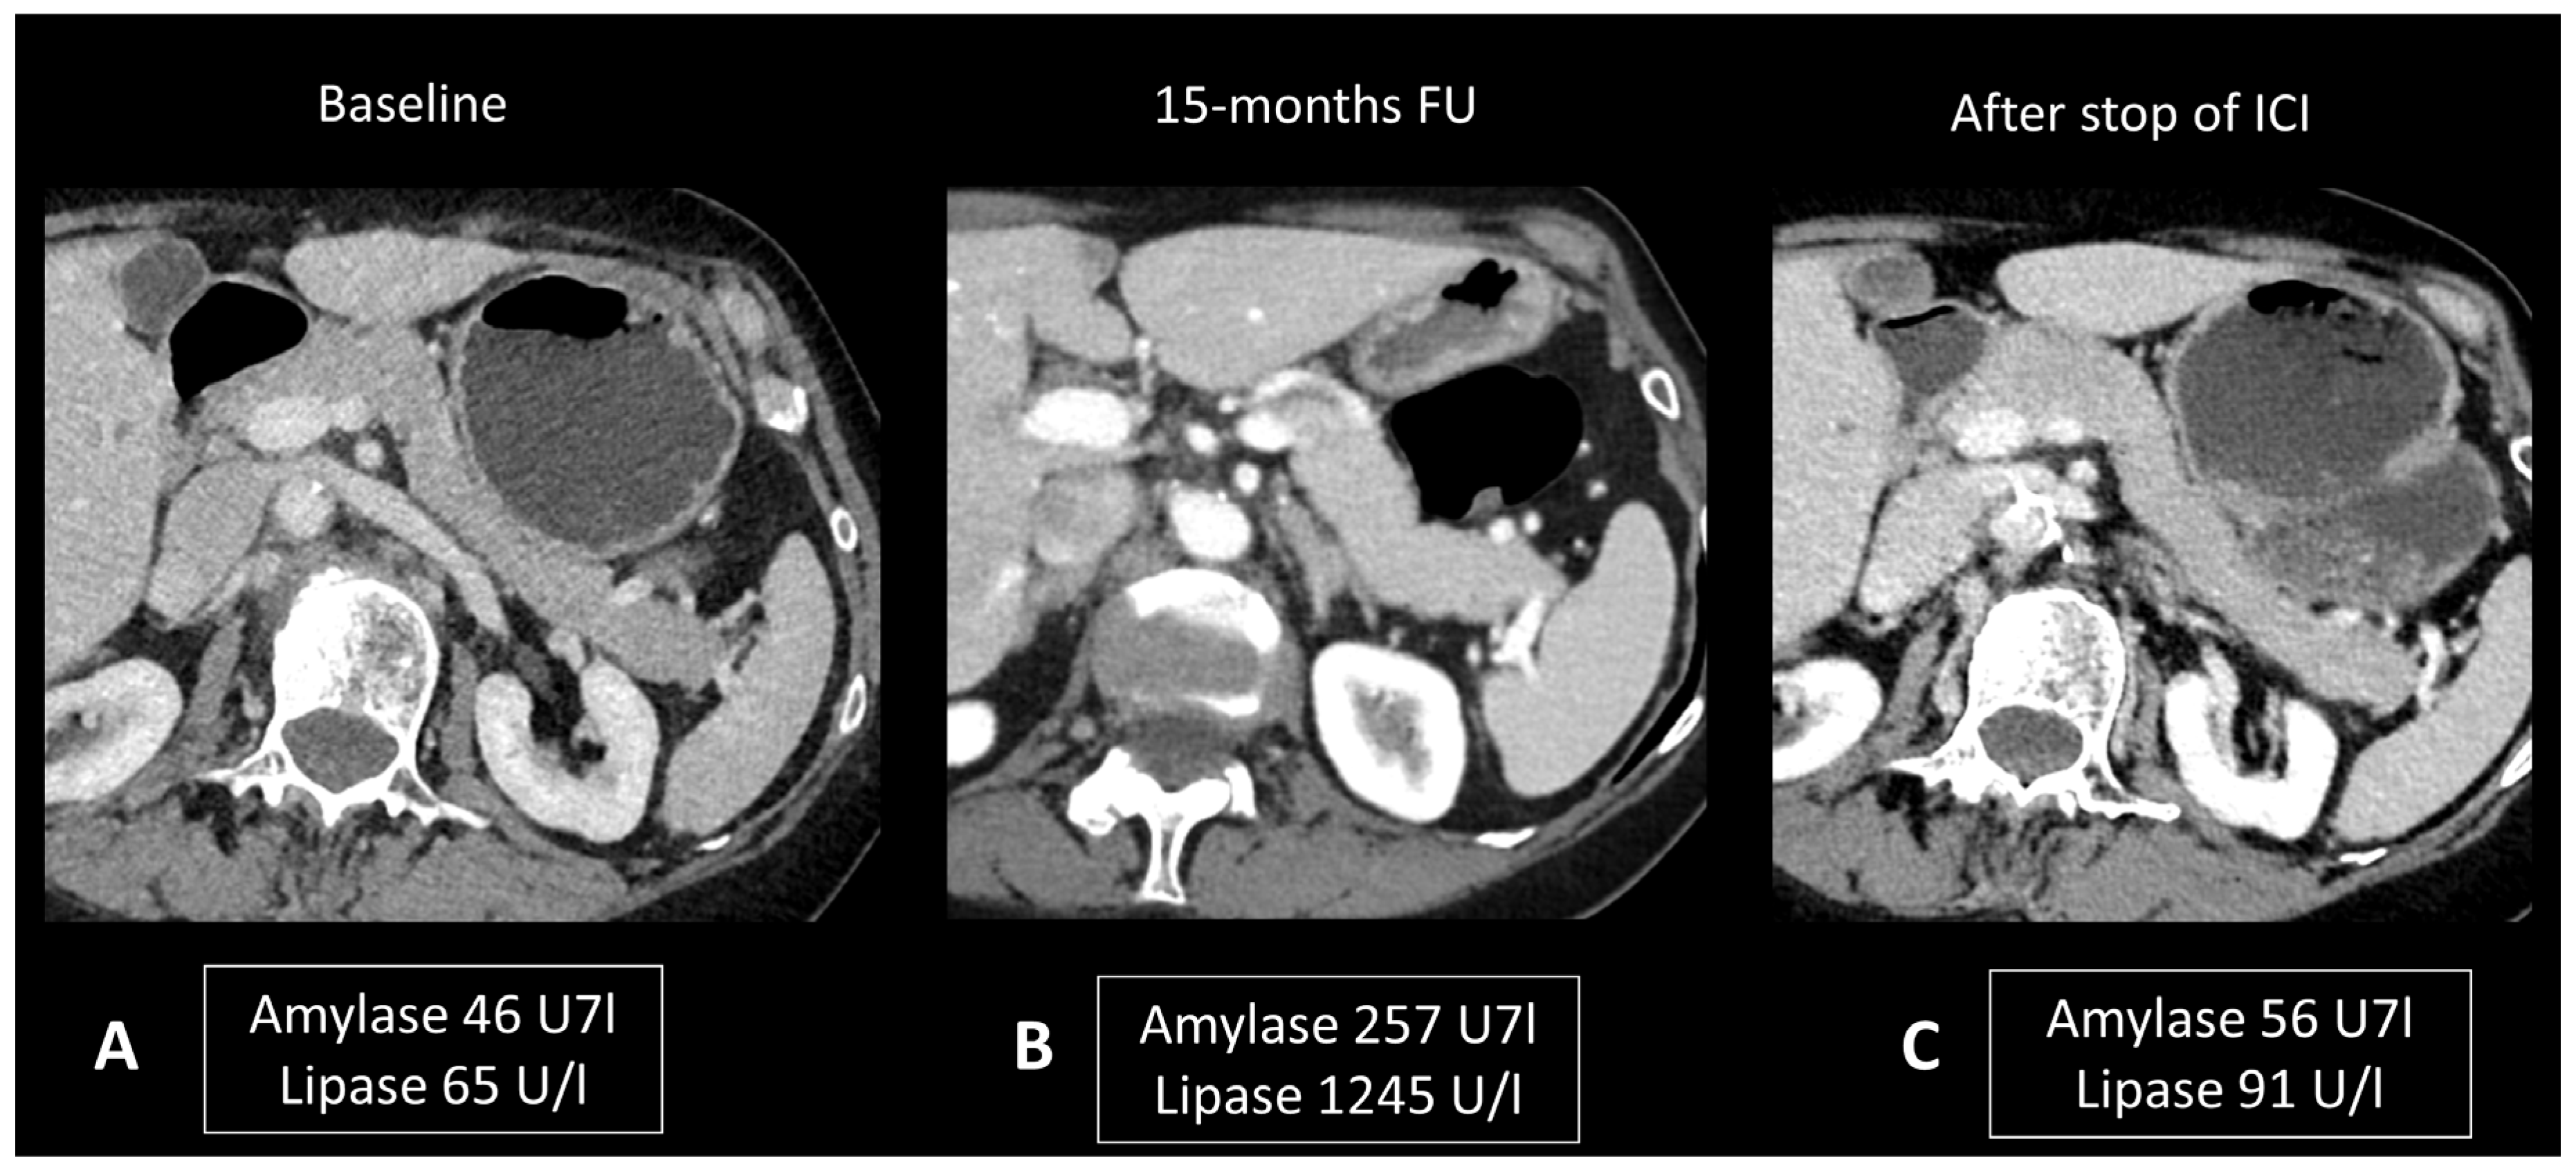

2.4.2. Ir-Pancreatitis

- Abu-Sbeih, H.; Tang, T.; Lu, Y.; Thirumurthi, S.; Altan, M.; Jazaeri, A.A.; Dadu, R.; Coronel, E.; Wang, Y. Clinical characteristics and outcomes of immune checkpoint inhibitor-induced pancreatic injury. J. Immunother. Cancer 2019, 7, 31. [Google Scholar] [CrossRef] [PubMed]

- Das, J.P.; Postow, M.A.; Friedman, C.F.; Do, R.K.; Halpenny, D.F. Imaging findings of immune checkpoint inhibitor associated pancreatitis. Eur. J. Radiol. 2020, 131, 109250. [Google Scholar] [CrossRef] [PubMed]

- Cherk, M.H.; Nadebaum, D.P.; Barber, T.W.; Beech, P.; Haydon, A.; Yap, K.S. 18F-FDG PET/CT features of immune-related adverse events and pitfalls following immunotherapy. J. Med. Imaging Radiat. Oncol. 2022, 66, 483–494. [Google Scholar] [CrossRef]